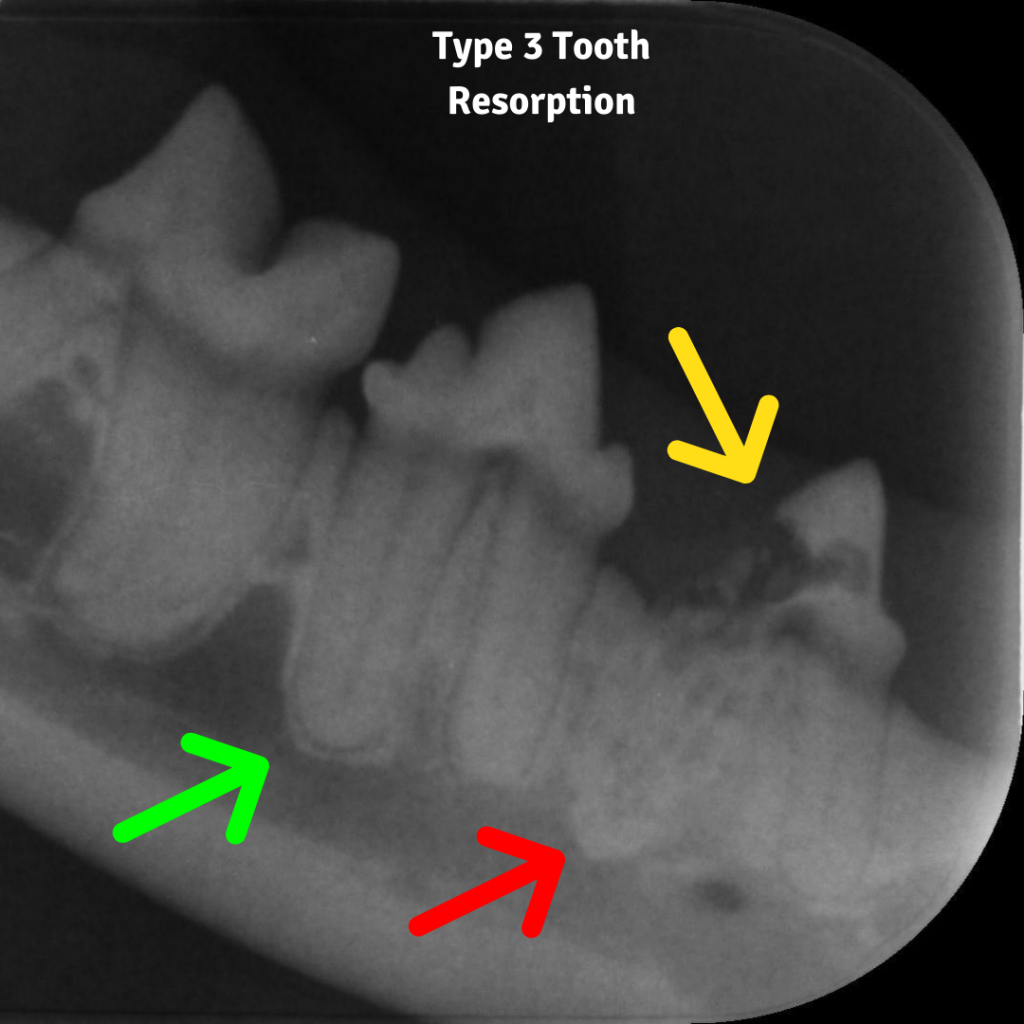

Type 3 lesions are a combination of both 1 and 2 lesions. There is focal resorptions above the gumline, but the root is also being resorbed and being replaced by bone.

This depends on the type of lesion. Type 1 lesions need to be completely removed. They are painful and cannot be removed by taking the exposed tooth away only, they need the entire root taken out as well. Type 2 and 3 can have crown amputations performed. As the root itself is already undergoing resorption and turning into bone, it often cannot be taken out and needs to be left. However in this situation, where the root is turning to bone, the root itself is not painful, and the pain resolves once the affected crown has been removed.